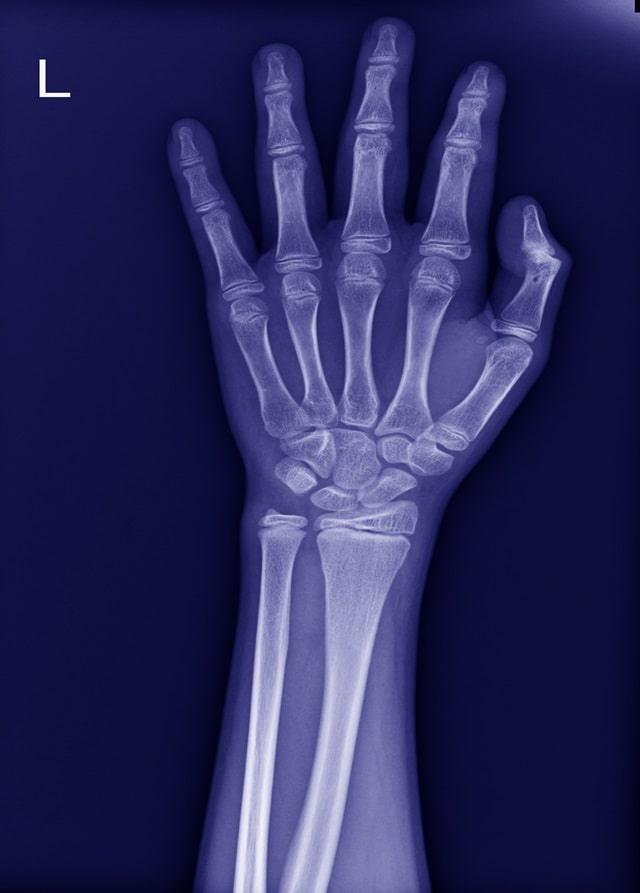

관절염은 관절에 통증, 경직 및 이동성 감소를 유발하는 전 세계 수백만 명에게 영향을 미치는 일반적인 질환이며,

가장 널리 퍼진 관절염 유형 중 두 가지는 손 골관절염 (hand OA)과 류마티스 관절염 (RA)입니다.

손 골관절염은 관절의 연골이 분해되는 것을 특징으로 하는 퇴행성 관절 질환입니다.

연골은 뼈의 끝을 완충하는 조직으로 관절의 움직임을 원활하게 해주는데 이 연골이 나빠지면 뼈가 서로 마찰하면서 해당 관절의 통증, 붓기, 뻣뻣함을 유발할 수 있습니다.

손 골관절염은 일반적으로 시간이 지남에 따라 점진적으로 발생하며 노인들에게 더 흔하지만, 젊은 사람들, 특히 관절 부상이나 과다 사용의 병력이 있는 사람들에게도 발생할 수 있습니다.